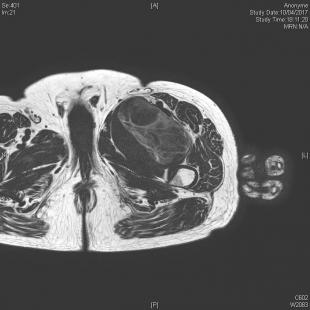

Néanmoins, c’est l’IRM qui est l’examen de référence. Sa version injectée permet de mieux distinguer lipomes, kystes synoviaux, tumeurs à cellules géantes, tumeurs nerveuses ou encore contenant une composante myxoïde (fig. 2 et 3). Mais, dans la majorité des cas, aucun diagnostic de certitude ne peut être obtenu à ce stade et la biopsie sera nécessaire avant d’entreprendre le traitement (fig. 1).